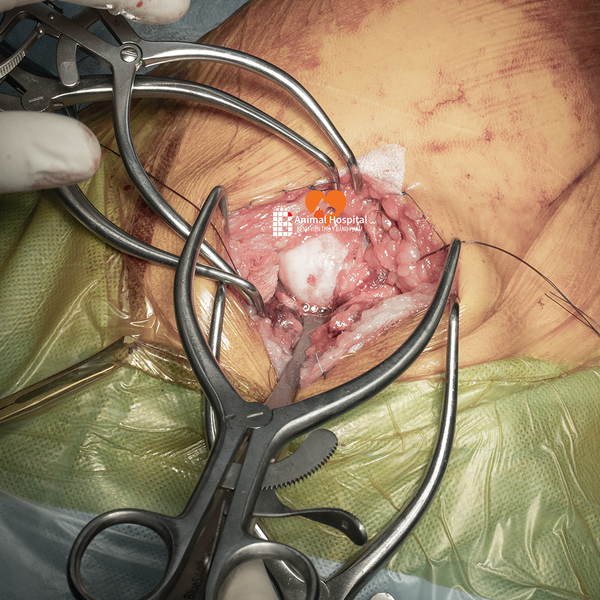

🔧 Giải pháp phẫu thuật | Total Hip Replacement (THR)

Sau khi đánh giá tổng thể tình trạng thoái hóa khớp háng ở chó, team bác sĩ tại Bệnh Viện Thú Y Bằng Phạm đã quyết định thực hiện thay khớp háng toàn phần bằng hệ thống tiên tiến 𝐁𝐥𝐮𝐞𝐒𝐀𝐎 𝐁𝐢𝐨𝐧𝐢𝐜 𝐇𝐢𝐩 – một trong những công nghệ hàng đầu hiện nay trong lĩnh vực cấy ghép khớp ở thú y.

✅ Đội ngũ phẫu thuật

- Bác sĩ phẫu thuật chính: Phạm Bằng, Nguyễn Đình Chuẩn, La Hạo Kiên

- Bác sĩ gây mê hồi sức: Kim Thao